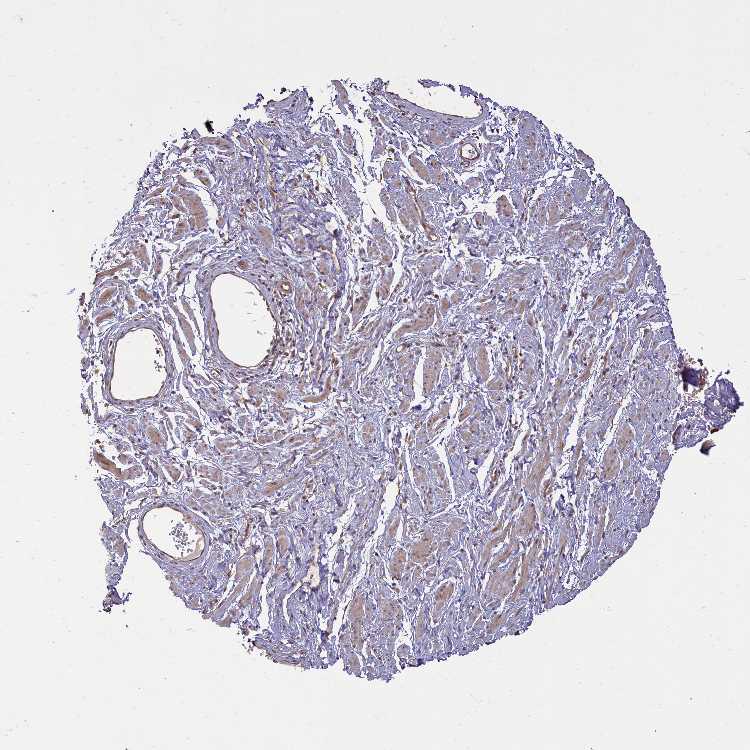

SOFT TISSUE 1 - Antibody stainingi

Antibody staining in the annotated cell types in the current human tissue is reported as not detected, low, medium, or high, based on conventional immunohistochemistry profiling in selected tissues. This score is based on the combination of the staining intensity and fraction of stained cells.

Each image is clickable and will lead to virtual microscopy that enables deeper exploration of all samples and also displays staining intensity scores, fraction scores and subcellular localization as well as patient and tissue information for each sample.

Antibody HPA041188

Chondrocytes Medium

Fibroblasts Not detected

Peripheral nerve Low